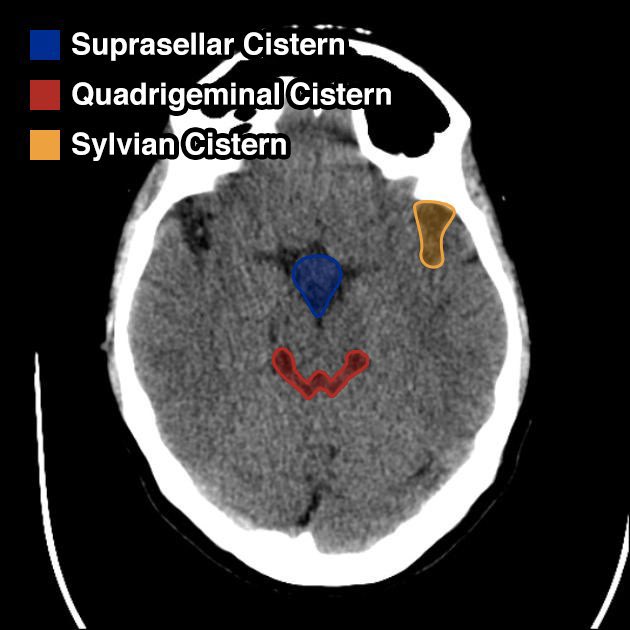

الحرف الثاني هو ال “C”

ويقصد فيه Cisterns

عبارة عن مساحات مليانة "CSF” ومتصلة ببعض عشان ال CSF circulation تمشي بسلاسة

Related pathology

Mass effect and ICP effacing 1 or more of the cisterns

Subarachnoid hemorrhage

arachnoid cyst